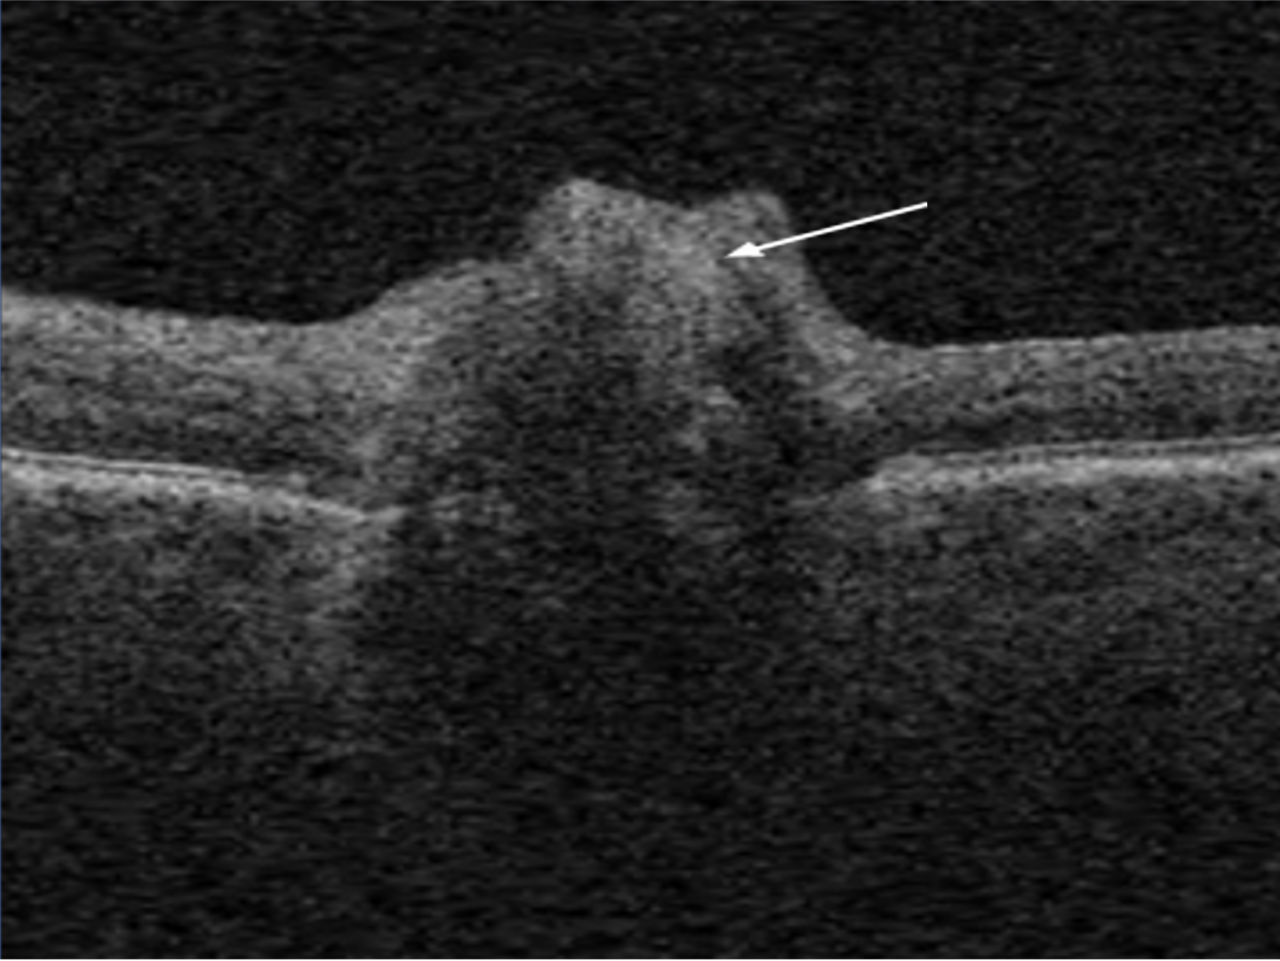

Bscan mode optical coherence tomography (OCT) in optic disk drusen Optical Disc Drusen Optic nerve drusen is a rare eye condition that affects between 3 and 24 people out of every 1,000 in the population. Optic nerve drusen can be mistaken for unilateral or bilateral disc edema and are often a source of. Unlike the drusen associated with amd, optic nerve drusen (also known as optic disc drusen) are not related to aging,. Optical Disc Drusen.